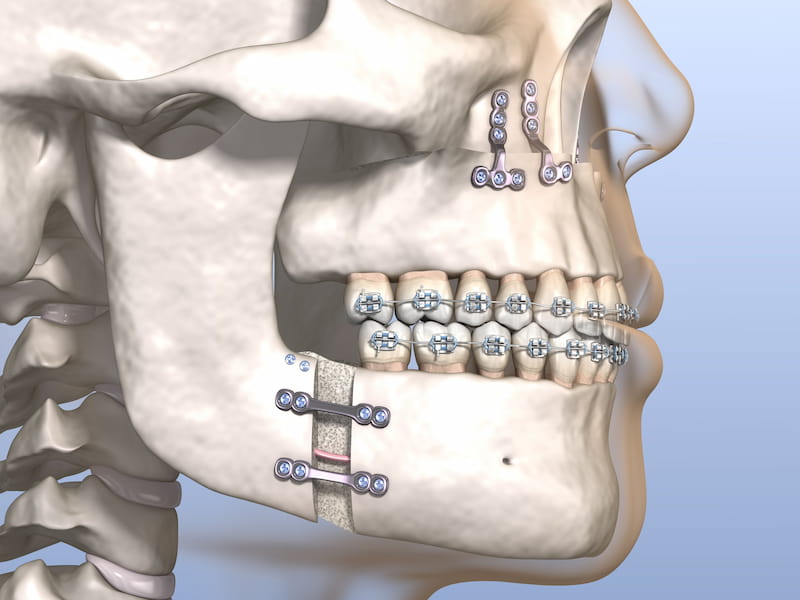

سپس، برای اصلاح زاویه فک و تعامل بین فکها، از پروتکلهای درمانی خاصی استفاده میشود که شامل تنظیم فشار و قدرت ایمپلنت، استفاده از براکتها و وسایل جانبی دیگر است.

پایه این ایمپلنت معمولاً از فولاد ضد زنگ یا تیتانیوم ساخته شده است.

دارای قابلیت تنظیم بالاست و میتواند برای اصلاح زاویه فک و تعامل بین فکها، از پروتکلهای درمانی خاصی استفاده کند.

از تیتانیوم ساخته شدهاند که مقاومت بالا و سبکی بیشتری نسبت به فولاد دارند.

باید قادر به تحمل فشار و نیروی زیادی باشد تا بتواند ناهنجاریهای فکی-دندانی را بهبود بخشد.